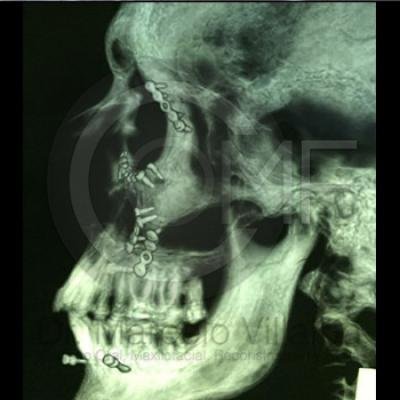

Fractura de Malar